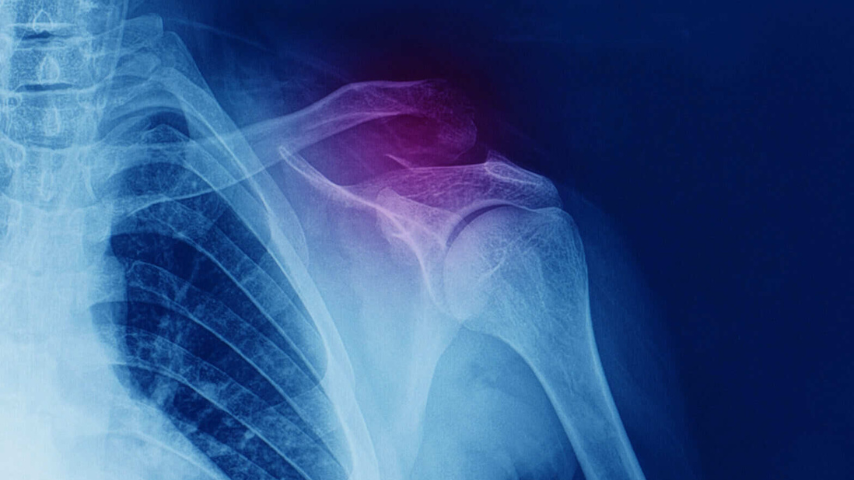

AC Joint Shoulder Dislocation

Specialty usually recommends an X-ray of the shoulder. Unless the damage is relatively severe, the X-ray may not reveal anything.

Its diagnosis is made by a detailed medical history, physical examination and an X-ray. X-ray is usually performed to confirm the joint separation and rule out any fracture to the clavicle. X-rays of opposite shoulder and rarely CT scan may be needed in some cases.

Your doctor will examine the afflicted region for pain, swelling, or deformation in order to diagnose and test it. The displacement of your shoulder joint can be seen on an X-ray, as well as any fractures or other damage.